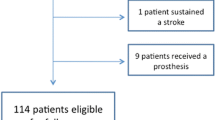

The preliminary analysis showed a failure rate of 20% for the control group instead of the expected 40%, and 12.9% for the augmented group. Given that the assumptions for the sample size calculation were wrong and the recruitment was very slow, the study was prematurely terminated after 67 patients had given informed consent and were randomized. The control group included 34 patients, of these 27 were eligible; the augmented group had 33 patients, of these 29 were eligible, Fig. 1.

Eleven patients were determined to be ineligible after randomization but were kept in the study. The reasons for ineligibility included: five patients had two-part fractures, one had a two-part fracture and the injury was older than 10 days, two had fractures older than 10 days, one had associated nerve/vessel injury, and two received implants other than PHILOS. Three more patients had protocol violation due to the following reasons: having more than four screws augmented, not having a leakage test performed before augmentation, and/or receiving screw augmentation despite joint perforation. In total, the treatment of 14 patients did not conform to the original protocol. Three patients from the augmented group crossed over to the control group due to positive leakage tests, resulting in 50 patients included for PP analysis.

The follow-up rate at 1-year was 85.1%: ten patients (seven from the control and three from the augmented group) dropped out. The reasons for dropping out were either unknown (two patients) or withdrawal of consent (eight patients) (Fig. 1).